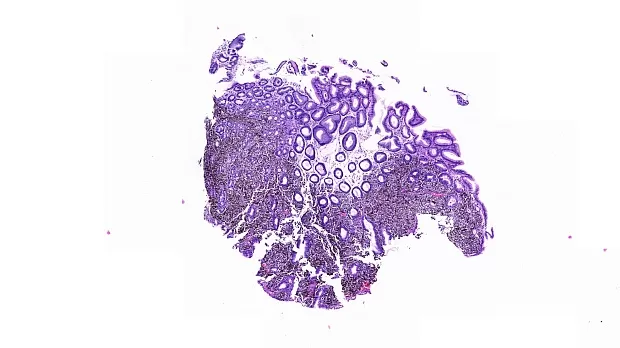

В луковице ДПК и постбульбарного отдела ДПК прослеживаются множественные пигментированные эпителиальные образования темно-черной-синей окраски, размерами до 5 мм, биопсия-гистология №1.

Заключение гистологии: В слизистой желудка рост пигментной эпителиоилноклеточной меланомы.